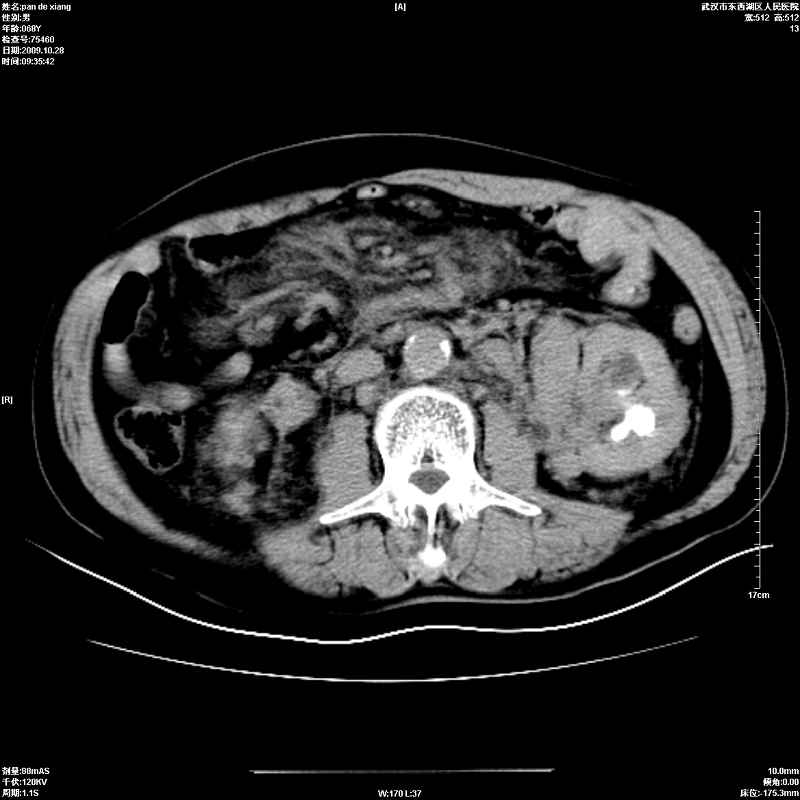

以下是引用杀毒软件在2009-10-28 20:41:00的发言:[br]结合临床考虑---白血病双肾改变或淋巴瘤。

以下是引用zxl51642在2009-10-29 9:59:00的发言:[br]结合临床“单克隆免疫球蛋白血症”,考虑双肾为继发损害并肾功能不全(尿中大量igg及少量iga、igm等大分子免疫球蛋白滤出所致继发损害),椎前软组织肿块为髓外造血。与浆细胞瘤有区别,平扫时有战友说的很清楚。